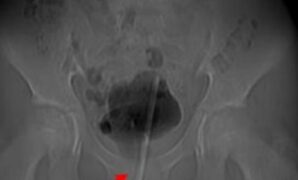

Petaka gegara Onani, Termometer Nyangkut di Alat Vital